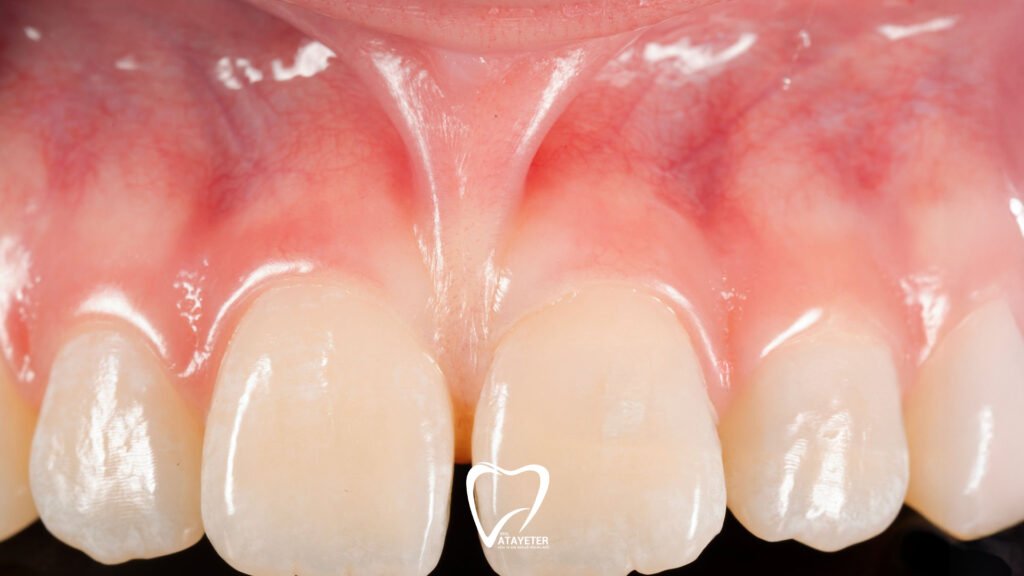

Ağız içinde en sık karşılaşılan frenulumlar; dilin alt kısmında yer alan dil altı frenulumu (lingual frenulum), üst dudağı diş etine bağlayan üst dudak frenulumu ve alt dudak ile diş eti arasında bulunan alt dudak frenulumudur. Bu dokular konuşurken kelimeleri doğru telaffuz edebilmemizden, yutkunmaya ve ağız içi hareketlerin doğal şekilde gerçekleşmesine kadar birçok temel fonksiyonda rol oynar.

Bunun dışında üst dudak frenulumu, ön dişler arasında açıklığa ya da diş eti çekilmelerine neden olabilir. Ayrıca ortodontik ya da protez tedavileri öncesinde, tedavinin sağlıklı ilerlemesi için frenektomiye ihtiyaç duyulabilir. Doğru zamanda yapılan bu küçük müdahale, uzun vadede büyük rahatlama sağlar.